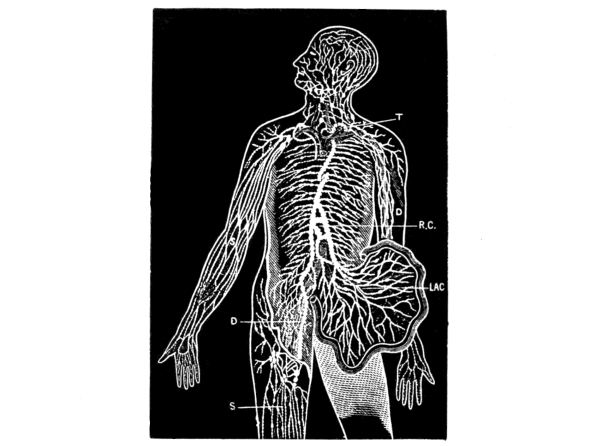

Lymphatic System.—The lymphatic system also extends throughout the body and consists of a system of channels, spaces, and glands very closely related to the circulatory system and containing a fluid called lymph. There are three principal parts to the system: 1. the lymph spaces, which are open spaces, with no definite walls, in the connective tissue framework of the body, more frequent near arteries and veins and especially so among the capillaries; 2. the lymph capillaries or small vessels which connect the lymph spaces; and 3. the lymphatic vessels, of which there is a deep and a superficial set, the latter accompanying the superficial veins on the surface of the body, the former accompanying the deep blood-vessels. [Pg 31]

Fig. 7.—Diagram showing the course of the main trunks of the absorbent system: the lymphatics of lower extremities (D) meet the lacteals of the intestines (LAC) at the receptaculum chyli (R.C.), where the thoracic duct begins. The superficial vessels are shown in the diagram on the right arm and leg (S), and the deeper ones on the left arm (D). The glands are here and there shown in groups. The small right duct opens into the veins on the right side. The thoracic duct opens into the union of the great veins of the left side of the neck (T). (Yeo.)

The lymphatic vessels have delicate, transparent walls, with three coats like the arteries, though much thinner, and anastomose even more freely than the veins. They have a beaded appearance due to the presence of numerous valves, which form constrictions on their surface. The right lymphatic duct, which is only about an inch long, drains all the lymphatics of the right half of the upper part of the trunk, the head, and the neck approximately, while the thoracic duct drains those of the rest of the body. The latter, which is the largest vessel of the [Pg 32] system, begins opposite the second lumbar vertebra with a bulb-like reservoir for the lymph or chyle, the receptaculum chyli, and extends up along the spinal column for a distance of about eighteen inches to the seventh cervical vertebra, where, with the right lymphatic duct, it empties into the left subclavian vein at its junction with the internal jugular, thus establishing direct communication between the lymph spaces and the venous system. The orifices of both vessels are guarded by semilunar valves to prevent regurgitation of the blood.